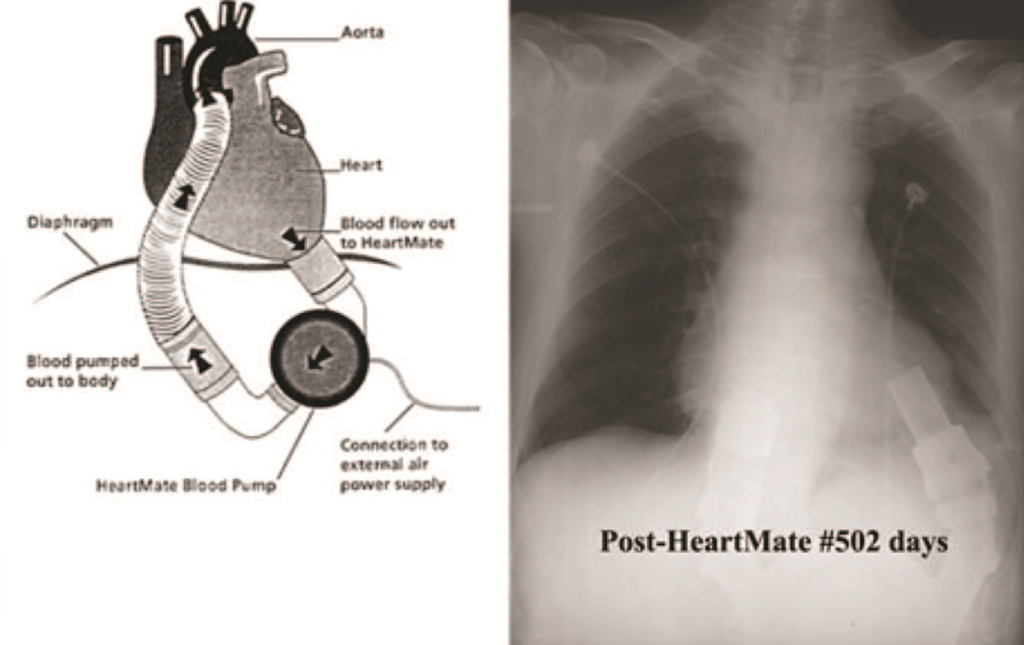

[ 대한민국 흉부외과의 발전 ]

134 국내 최초 Bridge to Transplant - 장병철 교수